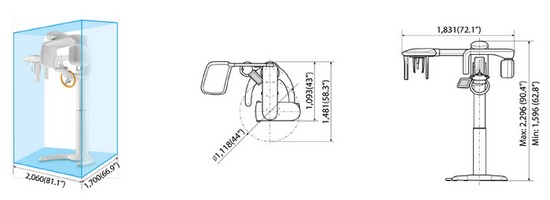

Rayscan a-SC (Alpha Pano Ceph) – панорамный рентгеновский аппарат последнего поколения с цефалостатом. Аппарат предназначен для панорамного сканирования зубов, челюстей и полости рта, а также включает в себя функцию сканирования для получения изображения головы. Специально разработанная конструкция аппарата позволяет в дальнейшем вне заводских условий произвести его дооснащение функцией компьютерной томографии (КТ). В стоимость аппарата входит мощный компьютер, программное обеспечение и беспроводной RF-пульт управления.

- Возможность дооснащения ортопантомографа с цефалостатом компьютерным томографом (далее КТ). В специальной конструкции аппарата предусмотрены технические возможности, позволяющие в дальнейшем ортопантомограф вне заводских условий дооснастить функцией КТ. Такой аппарат очень рациональное приобретение с поэтапным вложением средств. Ортопантомограф Alpha имеет компактный ультрасовременный дизайн, аппарат не только эффектно выглядит, но и занимает мало места в помещении.

- положение пациента: стоя или сидя

- диапазон регулировки опорной колоны по высоте: 700 мм

- вес: 176 кг